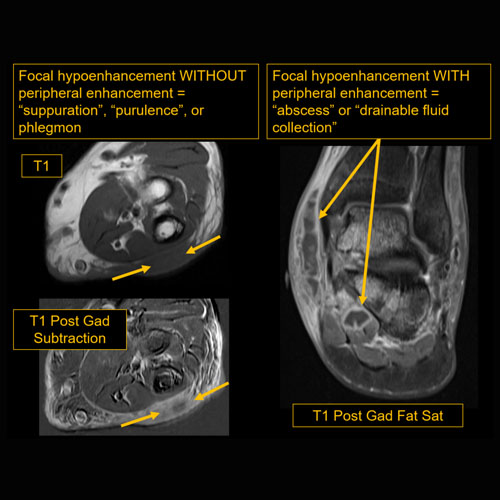

Section 1 Submit Findings CB1138 Findings Limitations There is patient motion or other limitations. Yes No Skin/Hypodermis There is edema or hyperenhancement. Yes No There is soft tissue ulceration or sinus tract. Yes No There is gas or foreign body. Yes No There is confluent hypoenhancement to suggest phlegmon, suppuration, abscess, or drainable fluid collection in the hypodermis. Yes No Investing/Intermuscular Fascia There is edema, thickening, or hyperenhancement. Yes No There is hypoenhancement or gas/susceptibility artifact. Yes No There is bulging of the fascia. Yes No Muscles There is edema or hyperenhancement. Yes No There is hypoenhancement, lack of enhancement, or organized fluid collection. Yes No There is fatty atrophy. Yes No Bones There are fractures. Yes No There is periosteal reaction, osseous destruction, or other abnormal marrow to suggest osteomyelitis. Yes No There is osseous hypoenhancement or lack of enhancement to suggest loss of bone viability. Yes No There is cloaca, sequestrum, or involucrum. Yes No There is a subperiosteal or intra-osseous abscess. Yes No Visualized Joints There is a joint effusion or synovitis. Yes No There is malalignment, degenerative changes, or other gross internal derangement. Yes No Miscellaneous There is tenosynovitis. Yes No Major visualized vascular structures are abnormal. Yes No Major visualized nerves are abnormal. Yes No